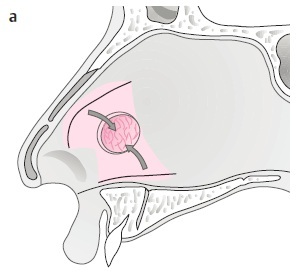

2. 選定模版: 在修補過程中,除了雙側鼻中隔黏膜外,會希望中間放置額外組織支撐並作為黏膜生長的模版。可選材料包含:骨膜(mastoid periosteum)、筋膜(temporalis fascia)、心包膜(pericranium)、鼻中隔軟骨/硬骨、 fascia lata、大腿外側筋膜,以及人工真皮(alloderm)。

→ 以價格考量:自體鼻中隔、耳軟骨或筋膜最適合、便宜又好用,其中以 Temporalis fascia 最常使用。

→ 以手術時間考量:Alloderm 或捐贈 fascia lata 較適合,不需額外取皮,縮短手術時間。

3. 手術方式(小洞): 如破損較小,可使用局部擴張或轉位(local flap),在內視鏡下以鼻中隔黏膜皮瓣或下鼻甲皮瓣修補。

4. 手術方式(大洞): 若破損較大,可考慮開放式鼻整形(Open rhinoplasty)修補,使用鼻道下方黏膜。

此方式為目前成功率最高的修補方式,也是最常使用的手術法。